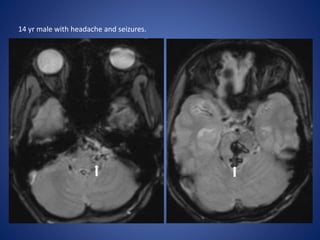

14 yr male with headache and seizures.

14 yr malewith headache and seizures.